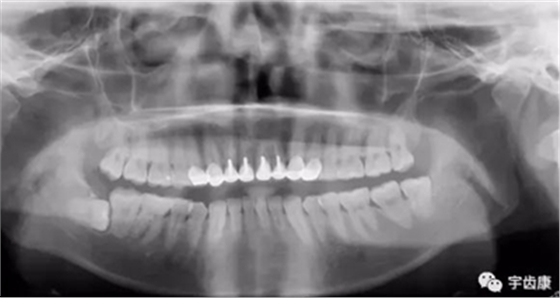

X線閱片知識